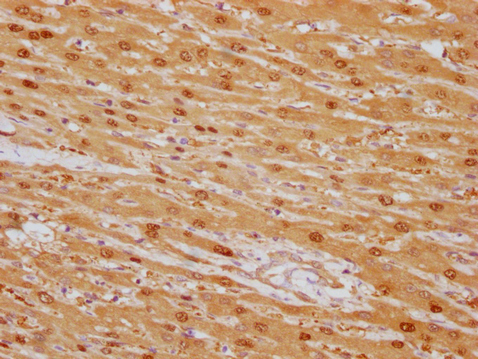

Human liver cancer

1:100